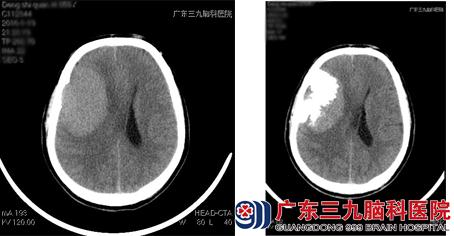

栓塞前与栓塞后对比图(左前右后)